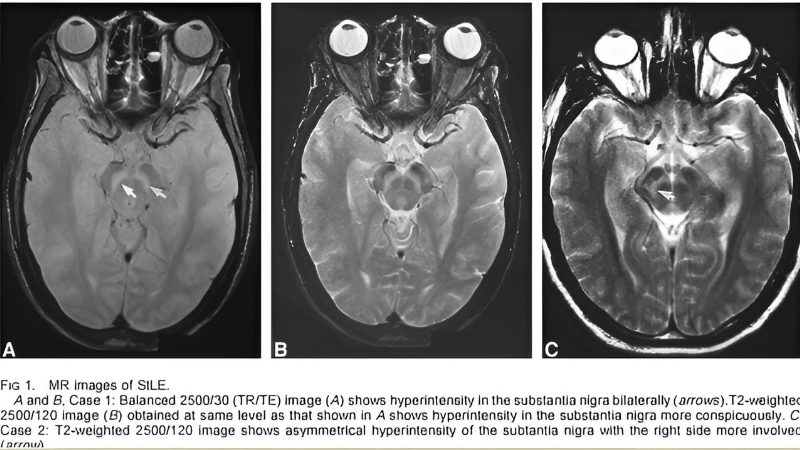

Image description of St. Louis Encephalitis

St. Louis Encephalitis is a mosquito-borne viral infection that affects the brain. The disease can cause flu-like symptoms or severe neurological complications in humans.